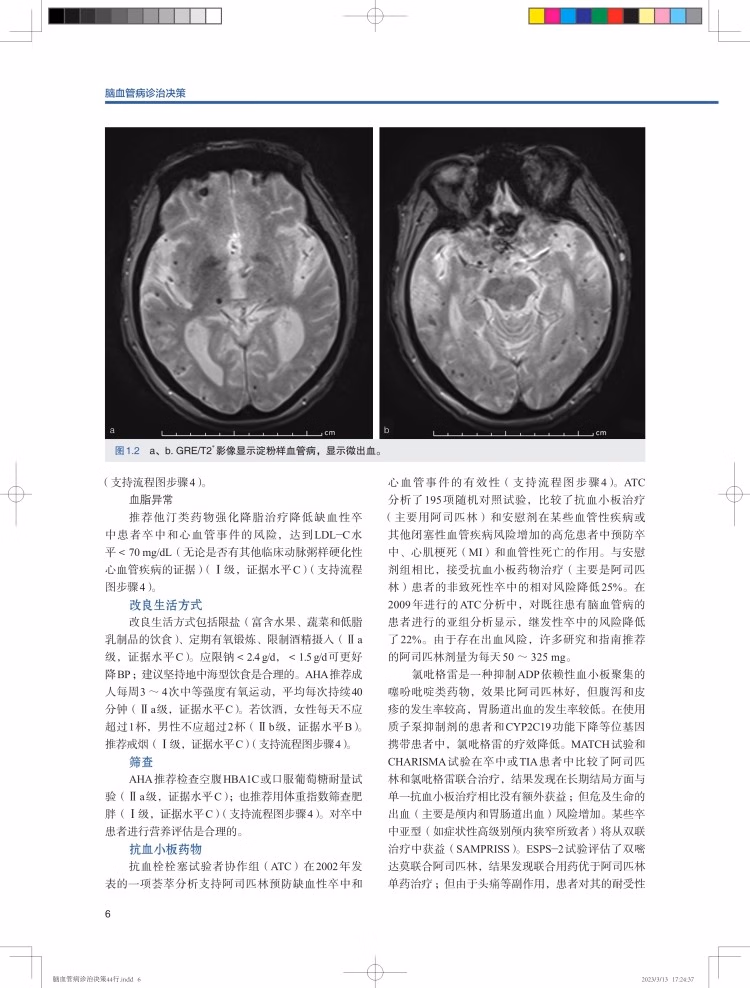

在线试读